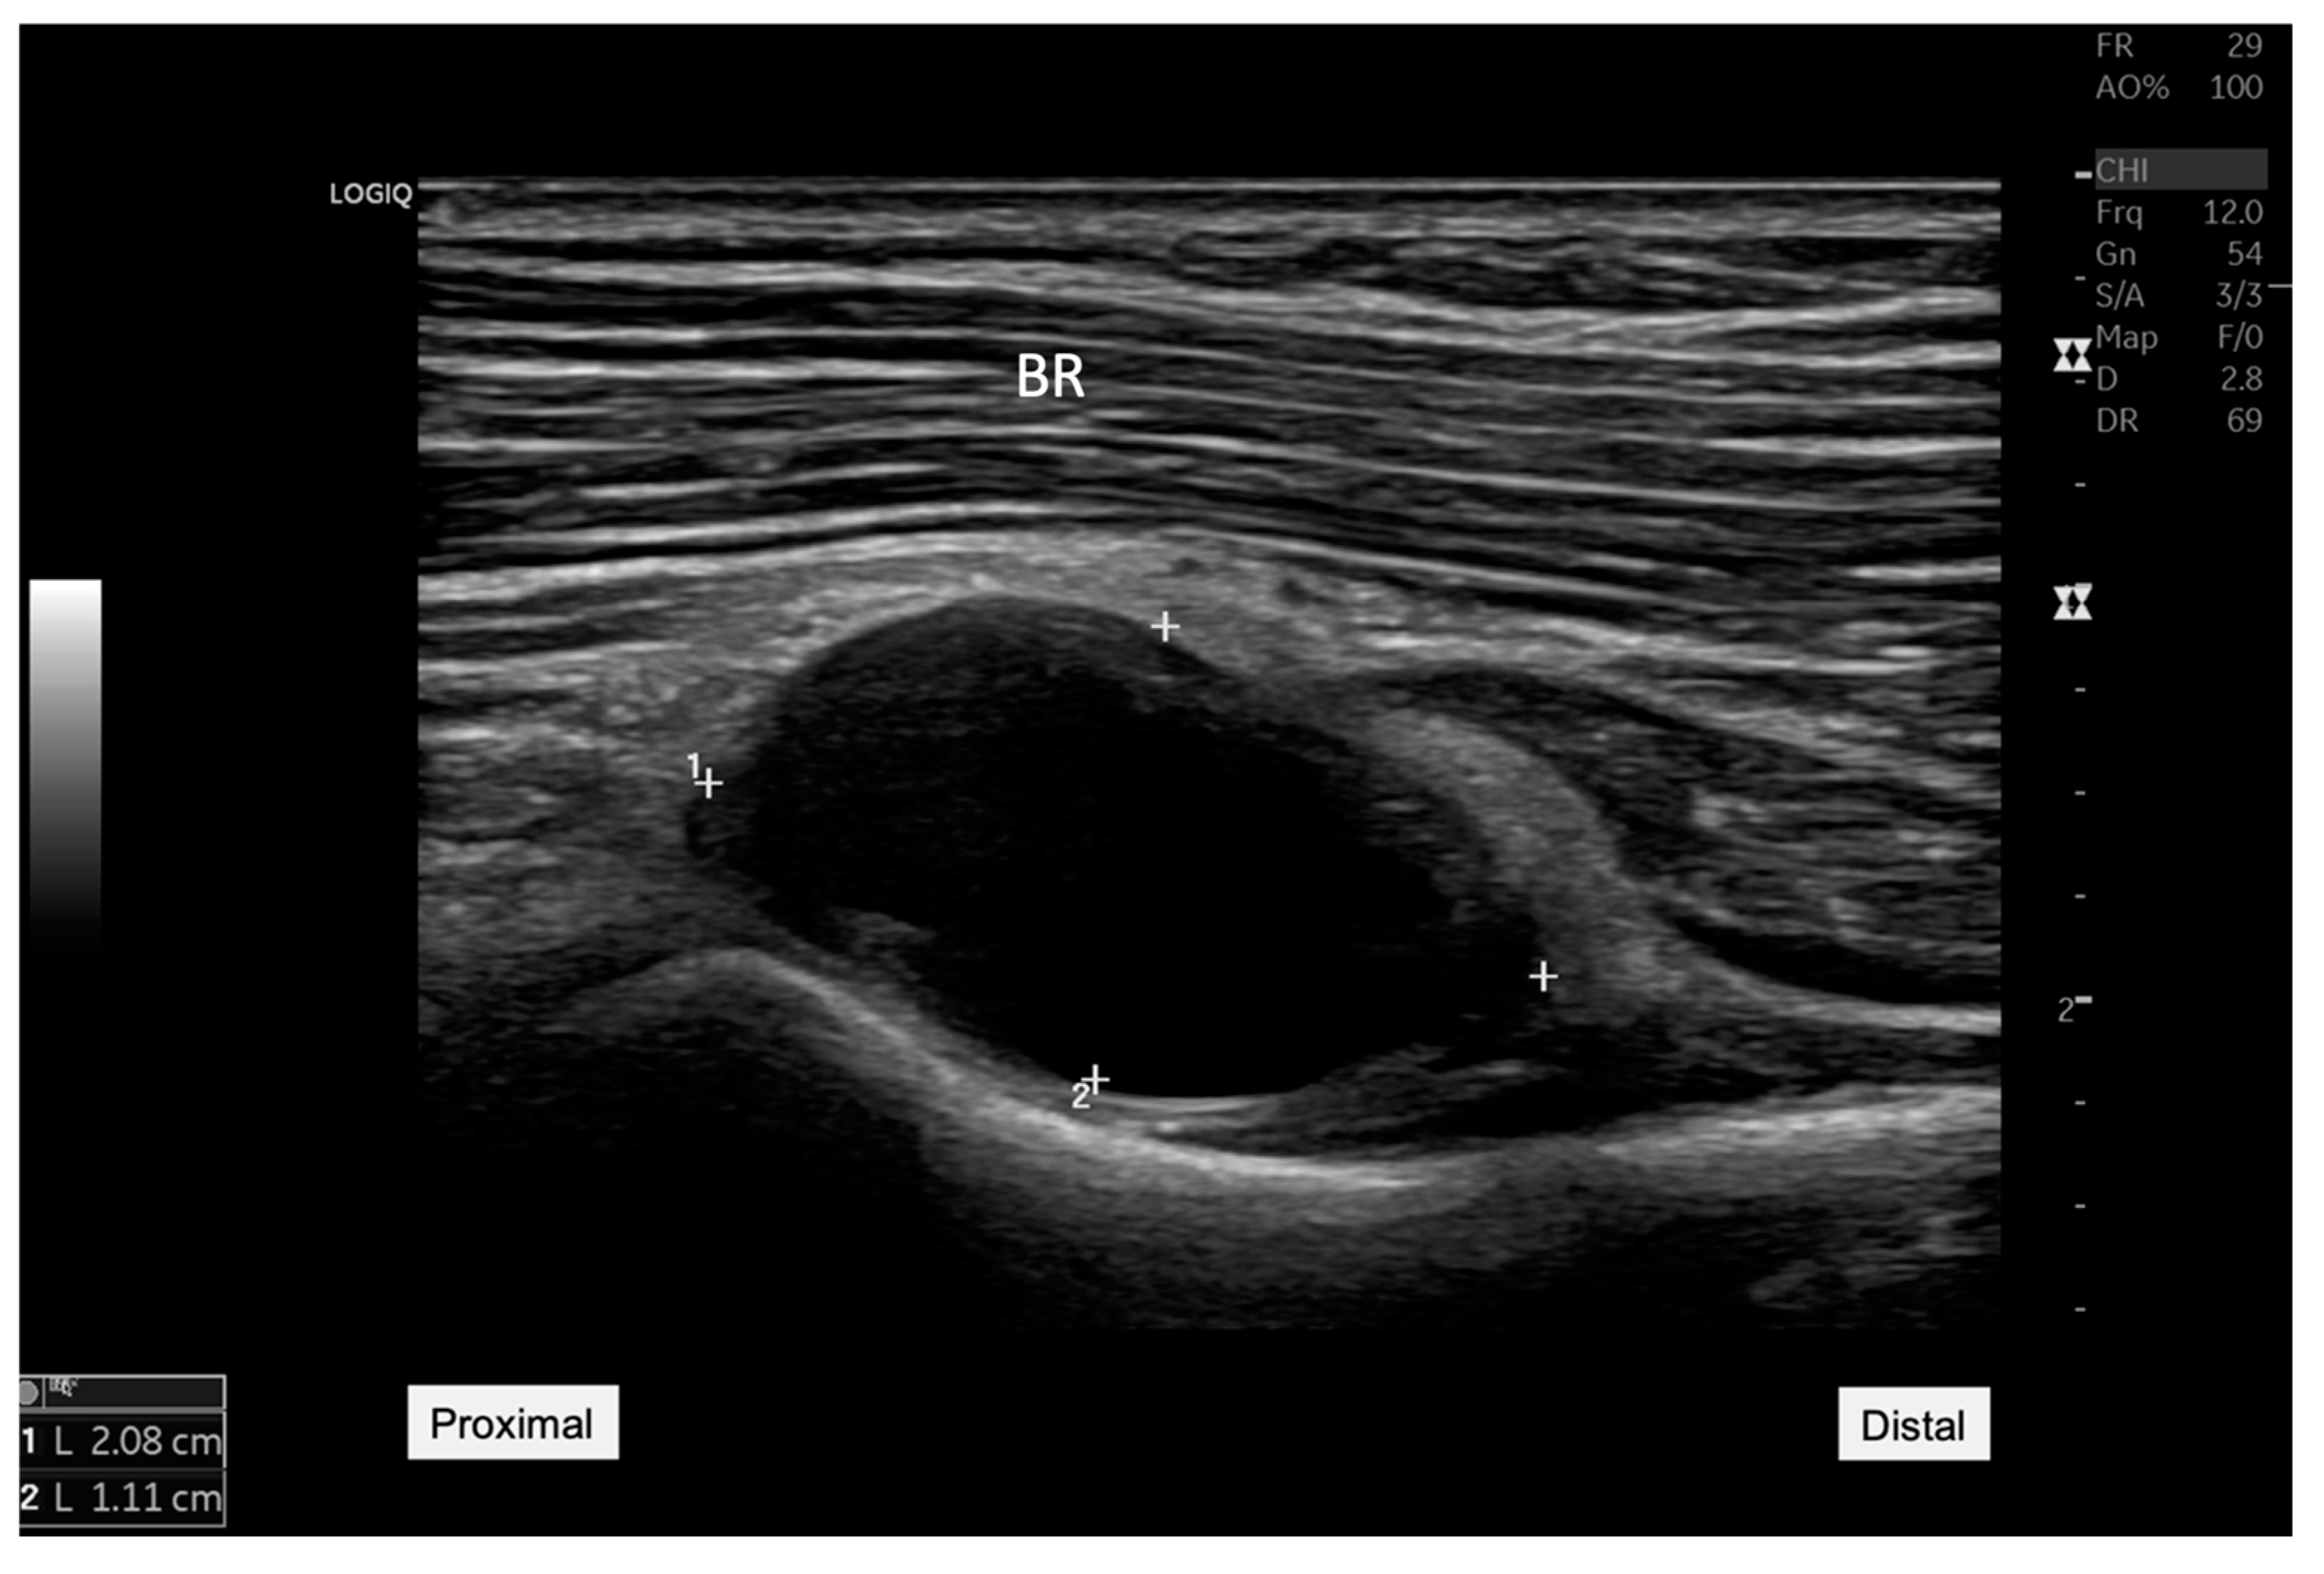

Ultrasound image showing an anechoic cyst measuring 20.8 mm by 11.1 mm located adjacent to the radiocapitellar joint. This finding was critical in reorienting the differential diagnosis toward the possibility of a synovial cyst impacting nearby neural structures. BR: Brachial radialis. A 45-year-old woman presented to our rehabilitation outpatient clinic with a three-week history of persistent pain and weakness in her right elbow and forearm, particularly exacerbated by wrist extension movements. Initial clinical assessments suggested possible lateral epicondylitis [

1], but the patient’s lack of response to standard conservative treatments prompted further diagnostic evaluation to explore underlying causes. On physical examination, manual muscle testing revealed significant weakness in right-hand extension involving all five fingers (grade 3 of 5) and wrist extension (grade 3 of 5). However, elbow extension remained strong (grade 5 of 5). Sensory examination revealed no deficits in the right hand or fingers, while the patient reported pain localized to the proximal forearm, notably exacerbated by wrist and finger extension movements. Electrophysiological testing revealed evidence of a conduction block with intact distal compound muscle action potential (CMAP) amplitude, suggesting radial nerve compression. Ultrasound examination was conducted using a GE LOGIQ P8 machine, with a 12-MHz linear transducer, ideal for detailed nerve and superficial soft tissue. Ultrasound imaging revealed a hypoechoic mass, measuring 20.8 mm by 11.1 mm near the radiocapitellar joint (

Figure 1.